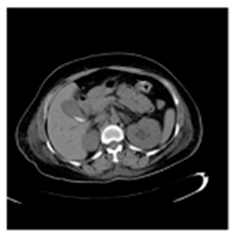

| Original Medical Images | |||||||

| Pair 1 | Pair 2 | Pair 3 | Pair 4 | ||||

![]() (1-9) PSNR = 44.14 | ![]() (1-10) PSNR = 41.90 | ![]() (1-11) PSNR = 40.09 | ![]() (1-12) PSNR = 41.41 | ![]() (1-13) PSNR = 42.24 | ![]() (1-14) PSNR = 40.35 | ![]() (1-15) PSNR = 40.79 | ![]() (1-16) PSNR = 40.84 |

| Shadow Images Produced by Using LSBs | |||||||

![]() (1-17) PSNR = 26.35 | ![]() (1-18) PSNR = 25.49 | ![]() (1-19) PSNR = 23.57 | ![]() (1-20) PSNR = 24.19 | ![]() (1-21) PSNR = 24.79 | ![]() (1-22) PSNR = 24.23 | ![]() (1-23) PSNR = 23.26 | ![]() (1-24) PSNR = 24.42 |

| Shadow Images Produced by Using Middle Bits | |||||||

![]() (1-25) PSNR = 18.97 | ![]() (1-26) PSNR = 19.95 | ![]() (1-27) PSNR = 14.10 | ![]() (1-28) PSNR = 13.84 | ![]() (1-29) PSNR = 16.66 | ![]() (1-30) PSNR = 13.23 | ![]() (1-31) PSNR = 13.38 | ![]() (1-32) PSNR = 14.75 |

| Shadow Images Produced by Using MSBs | |||||||